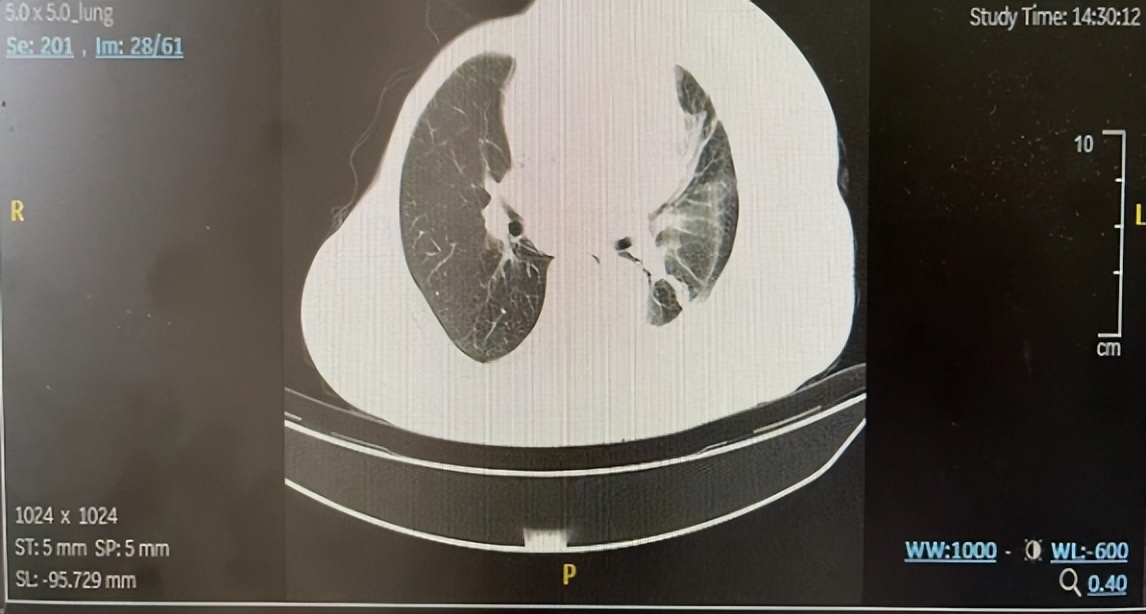

2022年8月起,患者接受戈沙妥珠单抗单药二线治疗,1周期后胸闷气喘明显好转,治疗2周期后(2022年9月)胸部CT:左锁骨区、纵隔多发淋巴结转移,部分较前减小(图4);左侧胸腔积液伴左肺部分膨胀不全较前好转(图5);左肺胸膜下治疗后改变可能同前;胸骨转移同前相仿;右侧锁骨骨质密度局部稍欠均同前相仿。

图4.纵隔淋巴结(左:基线;中:2周期后;最近一次复查)

图5.左侧胸腔积液(左:基线;中:2周期后;最近一次复查)